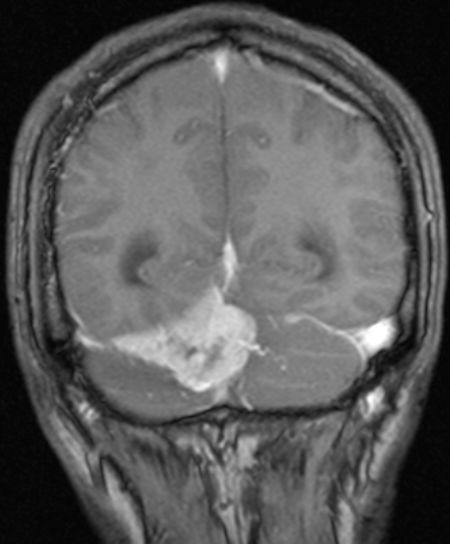

| MRT eines Meningeoms des Tentoriums |

| 72-jährige Patientin mit Teilparese des rechten Beins, passageren Sprachstörungen und Krampfanfall vor 6 Monaten. Postoperative Histologie: Meningeom Grad 1 | CT vor KM-Gabe . |